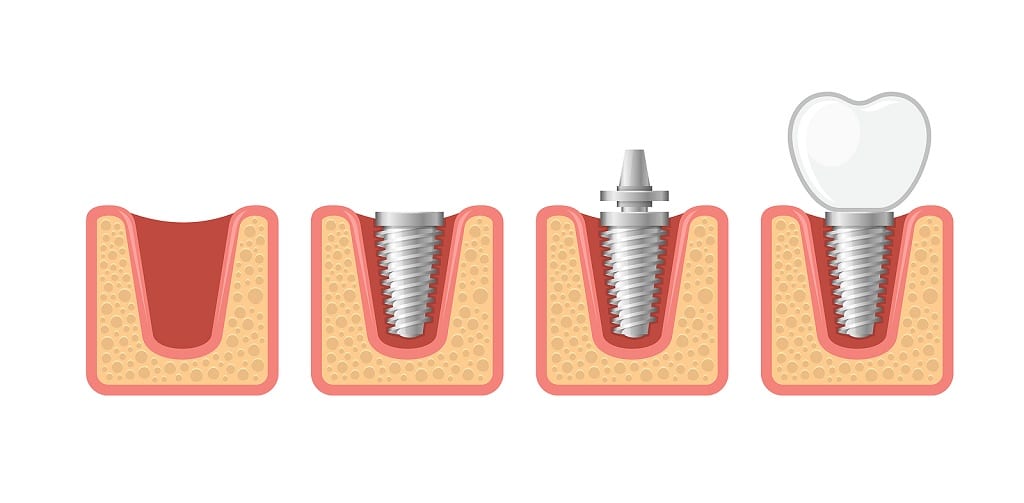

The dental implant itself is a small post anchored in the jawbone and serves as the “root” of the new tooth. The post, or screw, is typically made of titanium, which fuses with the existing bone of the jaw to form a permanent mount.

Once the screw, or root, is firmly anchored, the doctor will install an abutment to the top of the anchor. The abutment serves as the connector to lock the replacement tooth, called a crown, onto the screw.